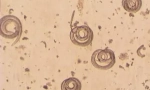

Potpuni Marx dizajniran je za vanjsku upotrebu iz ušiju. Lijek ne sadrži hemijske komponente, tako da ne šteti ljudskom zdravlju. Ovaj agent je uljna suspenzija svjetlosne nijanse sa specifičnim mirisom. Lijek u potpunosti niti je toksičan, princip njegove operacije je mehanički. Ako dođete do tijela parazita, ovjes ga omotava i preklapa se respiratorni trakt. Kao rezultat toga, insekt umire od gušenja.

Kada se obratite NITS-om, otopina slabi zaštitnu ljusku i neutralizira ljepilo, s kojom su pričvršćeni na kosu. Kao rezultat toga, kombinirani proces je pojednostavljen.